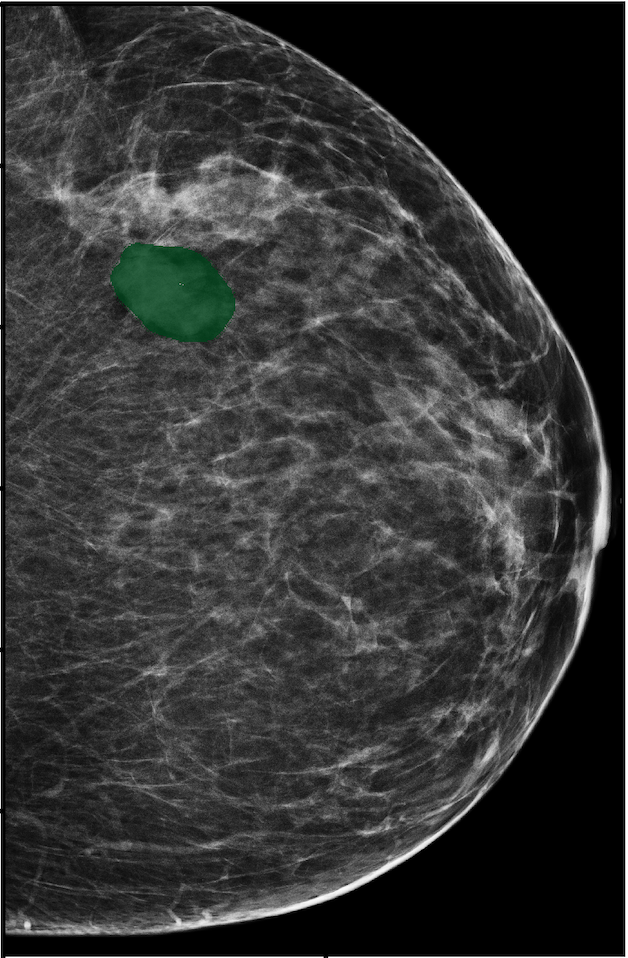

To evaluate the localization performance of GMIC, we select the model with the highest DSC for malignancy localization using the validation set. During inference, we upsample saliency maps using nearest neighbour interpolation to match the resolution of the input image. Our best localization model achieves a mean test DSC of 0.325 (std:0.231) for localization of malignant lesions and 0.240 (std:0.175) for localization of benign lesions. The best localization model achieves an AUC of 0.886/0.78 on classifying malignant/benign lesions. We observe that localization and classification performance are not perfectly correlated. The trade-off between classification and localization has been discussed in the weakly supervised object detection literature [15, 62, 82].

In Figure 7, we visualize saliency maps for four samples selected from the test set. In the first two examples, the saliency maps are highly activated on the annotated lesions, suggesting that our model is able to detect suspicious lesions without pixel-level supervision. Moreover, the attention is highly concentrated on ROI patches that overlap with the annotated lesions. In the third example, the saliency map for benign findings identifies three abnormalities. Although only the top abnormality was escalated for biopsy and hence annotated by radiologists, the radiologist’s report confirms that the two non-biopsied findings have a high probability of benignity and a low probability of malignancy. In the fourth example, we illustrate a case when there is some level of disagreement between our model and the annotation in the dataset. The malignancy saliency map only highlights part of a large malignant lesion with segmental coarse heterogeneous calcifications. This behavior is related to the design of : a fixed pooling threshold cannot be optimal for all sizes of ROI. The impact of is further studied in 3.6. This example also illustrates that while human experts are asked to annotate the entire lesion, CNNs tend to emphasize only the most informative regions. While no benign lesion is present, the benign saliency map still highlights regions similar to that in the malignancy saliency map, but with a lower probability than the malignancy saliency map. In fact, calcifications with this morphology and distribution can also result from benign pathophysiology [42].